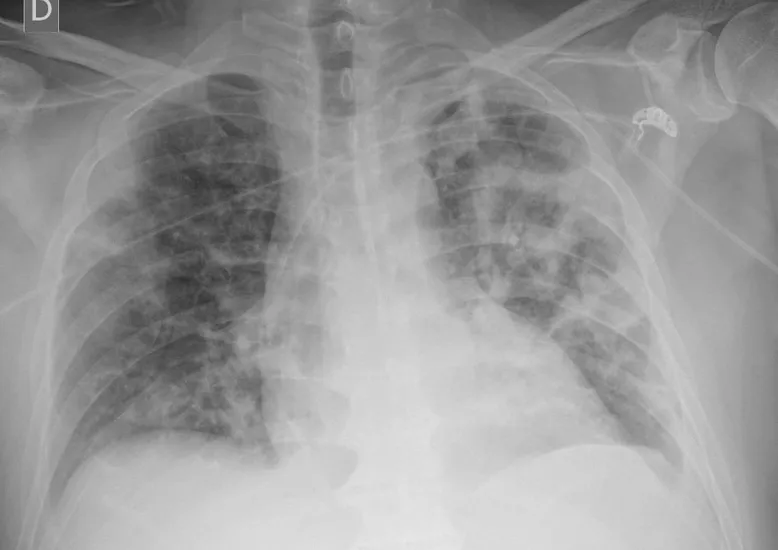

Distintas empresas con base en Argentina desarrollaron soluciones gratuitas para colaborar en diferentes aspectos que hacen a la mitigación de la expansión del coronavirus en el país. Nueva herramienta de detección de Covid-19 en radiografías de Tórax! Mauricio Farez explica en Diario Perfil los alcances y limitaciones de la herramienta en https://t.co/DtpKlDCZVk #COVIDー19

— entel_ai (@entel_ai) April 1, 2020